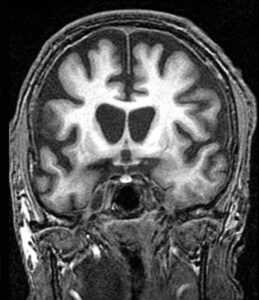

NBA PHOTO Huntington’s Disease Has Been Treated Successfully For The First Time In A Gene Therapy Trial by NBATitleChase • September 25, 2025 • Comments Off on PHOTO Huntington’s Disease Has Been Treated Successfully For The First Time In A Gene Therapy Trial Huntington’s Disease Has Been Treated Successfully For The First Time In A Gene Therapy Trial.